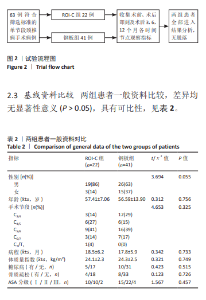

2.6 手术前后影像学评估 两组患者术后C2-7 Cobb角、T1倾斜角,椎间隙高度均较术前显著改善,两组组内不同时间点的C2-7 Cobb角、T1倾斜角,椎间隙高度比较存在显著差异(P < 0.001),而不同分组之间的评分差异无显著性意义(P > 0.05),并且两组在不同时间点的趋势也无显著差异(P > 0.05)。 ROI-C组术后即刻、术后3,6,12个月的C2-7 Cobb角、手术节段椎间隙高度及术后3,6个月的T1倾斜角较术前均显著增加;术后3,6,12个月的C2-7 Cobb角、术后3个月的T1倾斜角均较术后即刻明显增加;术后6个月的C2-7 Cobb角较术后3个月明显增加,差异有显著性意义(P < 0.05)。钢板组术后即刻、术后3,6,12个月的C2-7 Cobb角、手术节段椎间隙高度及术后即刻、术后3,6个月的T1倾斜角均较术前明显增加;与术后即刻相比,钢板组术后3,6,12个月的C2-7 Cobb角及术后3,6个月的T1倾斜角均明显增加;术后6个月的C2-7 Cobb角较术后3个月明显增加,术后12个月的T1倾斜角较术后3个月明显减小;术后12个月的T1倾斜角较术后6个月明显减小,差异有显著性意义(P < 0.05)。见表5。"